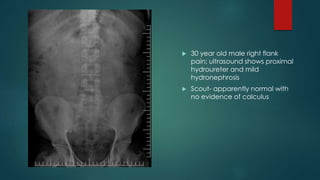

 30 year old male right flank

pain; ultrasound shows proximal

hydroureter and mild

hydronephrosis

 Scout- apparently normal with

no evidence of calculus

 10 min film- right sided proximal

hydroureter and mild dilatation of

pelvicalyceal system

 15 min film- findings are persistent and

a filling defect is noted at the L3-L4

level